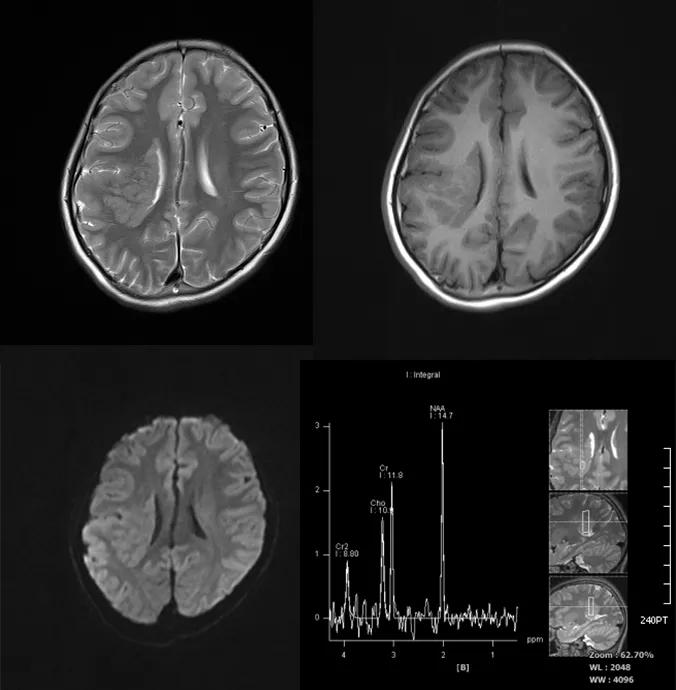

case 1:女性 ,14 岁,反复癫痫发作。

诊断:右侧脑室旁灰质异位。